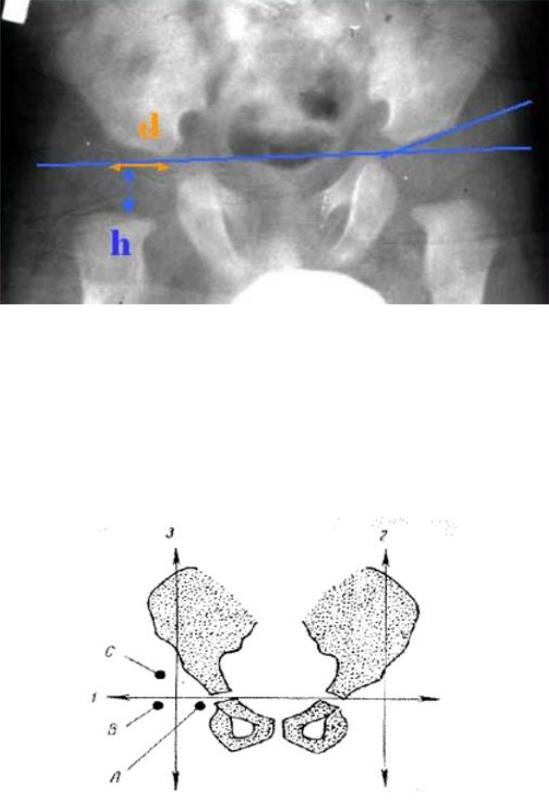

г) определяют дистанцию α – расстояние от дна вертлужной впадины до перпендикуляра h на линии Келлера (в норме = 10-12 мм.).

Рис. 70. Схема Рейнберга

Рис. 71. Схема Хильгенрейнера.

Величина h, указывающая нам о вертикальном смещении головки относительно вертлужной впадины - расстояние от горизонтальной линии Хильгенрейнера до середины метафизарной пластинки проксимального отдела бедра.

В норме эта величина одинакова с обеих сторон и составляет от 9 до 12

мм. Снижение этого показателя и его различие справа и слева свидетельствуют о наличии патологии.

Величина d, указывающая о латеральном смещении головки бедра относительно вертлужной впадинырасстоянии от дна вертлужной впадины до вертикальной линии (величины h).

При нормальном развитии тазобедренных суставов она также одинакова с обеих сторон и должна быть не более 15 мм.

Схема Хильгенрейнера удобна, надежна, дает объективные представления о тазобедренном суставе, а при умении читать рентгенограммы довольно проста (Рис. 72).

Большим ее достоинством является то, что она позволяет рано выявить незначительные смещения бедренной кости кнаружи и кверху.

Рис. 72. Схема Хильгенрейнера. АИ < 30, h = 9-12, d < 15